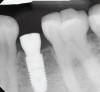

Radiographs taken at time of implant placement (Figure 4) and at the time of prosthesis installation (Figure 5) should serve as baseline radiographs.4,14,15 If clinical signs suggest the presence of peri-implantitis, a new periapical or bitewing radiograph of the site should be taken and compared with baseline to confirm or negate the initial diagnosis. Radiographs have limitations when bone loss presents on the buccal or lingual of the implant.15 Careful consideration is warranted when determining the difference between adaptive bone remodeling and creation of the supra-crestal attached tissues (biologic width) that occurs around non-platform switched implants, as well as bone loss with the presence of clinical signs of inflammation due to disease.

Figure 4. Radiograph at the time of implant placement.

Figure 4

Figure 5. Radiograph at the time of prosthesis installation.

Figure 5